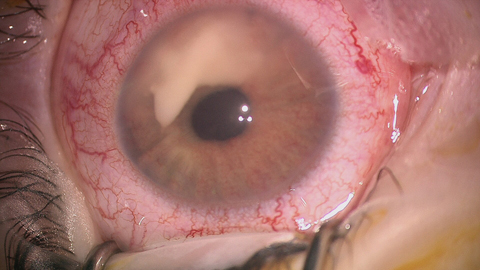

Conjunctival ulcers: a rare feature of ocular herpes simplex virus infection